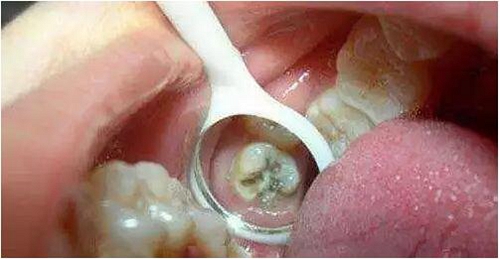

*牙髓炎:深齲由于齲洞離牙髓比較近,齲洞內(nèi)的細菌和細菌所產(chǎn)生的毒素容易滲透到牙髓組織,引起牙髓炎,使患牙發(fā)生劇烈疼痛。這個階段,根管治療是唯一可行的辦法。治療時需要麻醉后將牙髓組織清除,即大家所說的“殺神經(jīng)”。

*根尖炎:牙髓炎得不到及時治療,或治療不徹底,細菌可通過牙髓向根尖擴散,引起牙齒根尖部的病變,如根尖炎、根尖周炎、根尖膿腫等不同疾病。根尖部的病變急性發(fā)作時也會引起較重的疼痛,甚至牙齦及面部腫脹。根尖炎也需要行根管治療。